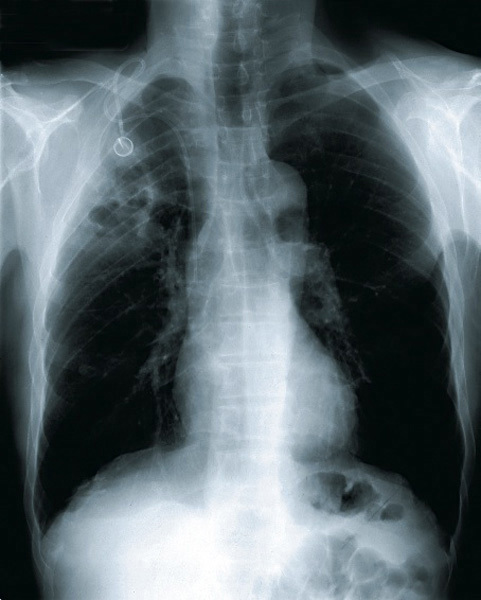

©La Revue du Praticien Opacité du segment apical du lobe supérieur droit avec hyperclartés multiples traduisant le processus nécrosant, caractéristique des bactéries anaérobies, encore appelée pneumonie nécrosante